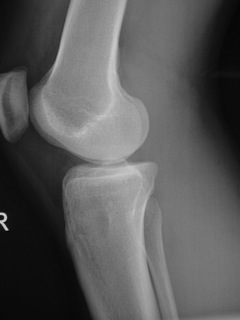

• Lytic lesion (Fig. 1, Fig. 2 & Fig. 3)

• Well-defined

• Geographic margins

• Eccentric

• Majority have well-defined sclerotic rims

• More aggressive lesions may have irregular margins

• Frequently produce endosteal erosion and cortical thinning

• Trabeculation may be seen

• In long bones, metaphysis, epiphysis, or diaphysis may be involved

Fig. 2

Fig. 1-3: AP and Lateral plain x-rays of a benign fibrous histiocytoma shows an eccentric lytic lesion in the proximal tibia, well- demarcated with a prominent sclerotic rim. No soft tissue mass or trabeculations are seen.